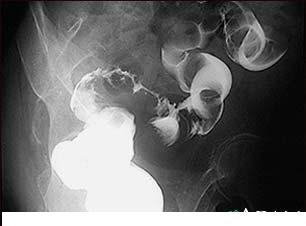

Profilaxia cancerului colorectal